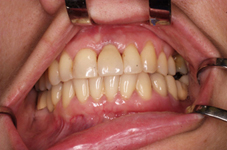

V případě chybění většího počtu zubů v postranních úsecích čelistí je možné ošetření pomocí implantátů, které nahradí ošetření pomocí snímacích náhrad kotvených na zbývajících zubech nebo patře.

Podmínkou je opět dostatečné množství kosti.

Protetické řešení může být pomocí můstku, který je kotvený na implantátech nebo pomocí jednotlivých korunek na implantátech.

V zásadě je možné do těchto můstků zařadit i přirozené zuby, zejména pokud je potřeba tyto zuby ošetřit proteticky – korunkami. Korunky nebo můstky mohou být na implantáty nacementovány nebo přišroubovány.

Zdravé zuby zůstanou zachovány a přitom náhrady jsou pevné, jako na vlastních zubech